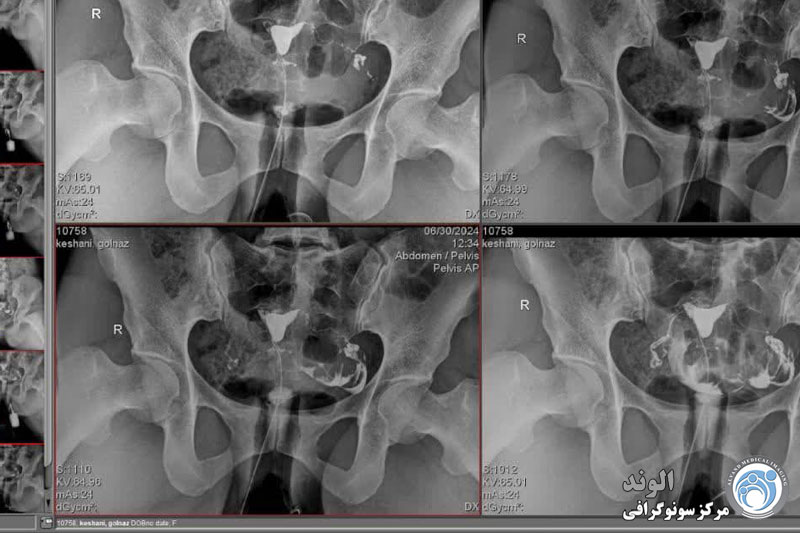

هیستروسالپنگوگرافی؛ هیستروسالپنگوگرافی (HSG) نیز نامیده می شود، هیستروگرافی یک معاینه اشعه ایکس از رحم و لوله ها است. در سال های اخیر، به طور فزاینده ای با تصویربرداری رزونانس مغناطیسی (MRI) جایگزین شده است. هیستروگرافی در مطب رادیولوژی توسط رادیولوژیست انجام می شود.

هیستروسالپنوگرافی یک معاینه رادیوگرافی برای مشاهده رحم (= هیسترو) و لوله های فالوپ (= سالپنگو) با استفاده از یک محصول غیر شفاف نسبت به اشعه ایکس، تزریق شده به داخل حفره رحم است.

بیمار در وضعیت زنان (به پشت خوابیده، زانوهای خم شده و از هم باز)، زیر دستگاه اشعه ایکس قرار می گیرد. پزشک یک اسپکولوم را وارد واژن میکند، سپس یک کانولا را در دهانه رحم قرار میدهد که از طریق آن یک ماده حاجب تزریق میکند. این به داخل رحم و لوله های فالوپ گسترش می یابد. اشعه ایکس برای مشاهده پیشرفت خوب محصول و تجسم اندام ها گرفته می شود.

هیستروسالپنگوگرافی توسط رادیولوژیست انجام می شود. معاینه بدون بیهوشی انجام می شود. بیمار در موقعیت "زنان و زایمان" مستقر می شود. پزشک اسپکولوم را قرار می دهد، دهانه رحم را ضد عفونی می کند و سپس یک پروب را با روش طبیعی وارد رحم می کند. او به تدریج ماده حاجب را تزریق می کند. به طور معمول، ماده حاجب به تدریج رحم و لوله های فالوپ را کدر می کند تا زمانی که به حفره صفاقی منتقل شود.

چندین عکس رنگی رحم قبل، حین و بعد از تزریق محصول گرفته می شود و این در موقعیت های مختلف:

اشعه ایکس بدون آماده سازی (جستجو برای کلسیفیکاسیون لگن)؛

اشعه ایکس پر شدن ضعیف (پولیپ ها یا فیبروم های زیر مخاطی را برجسته می کند).

اشعه ایکس پر شدن لوله (ارزیابی وضعیت مخاط لوله).

عکس پروفایل (ارزیابی موقعیت رحم و مسیر لوله های فالوپ)؛

اشعه ایکس دیررس (بررسی گردش خون صفاقی، جستجو برای چسبندگی لگن).

در اصل، HSG یک ارزیابی رادیوگرافی از حفره رحم و لوله های فالوپ با استفاده از فلوروسکوپی سرپایی بلادرنگ با تزریق ماده حاجب رادیویی مات از طریق کانال دهانه رحم را نشان می دهد. کانال دهانه رحم، کانتور حفره رحم و لومینای رحم و لوله شامل بخش های قرنیه، ایستمی و آمپولری و تعیین